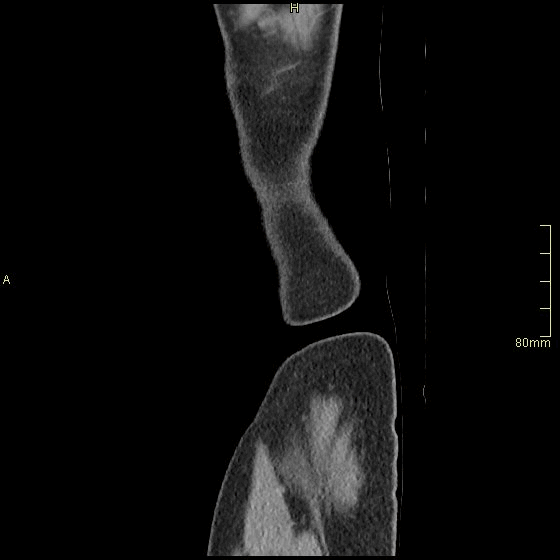

Portal Venous Abdomen (Sagittal)